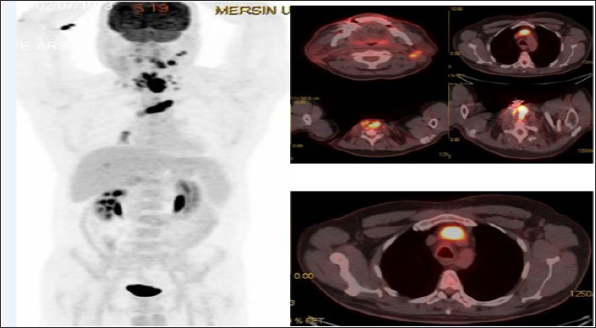

Figure 1: MIP (Maximum Intensity Projection) image and axial fusion images demontrate left brachiosephalic vein TT with SUVmax: 19.45 in a recurrent laringeal cancer 42 year old male patient.

FDG-PET/CT imaging performed for staging, restaging and treatment response in oncological patients and patients with suspected malignancy. A total of 37 patients with tumor thrombus and benign thrombus were included. Patients who had confirmed primary malignancies ( lung cancer in 7 patients, gastrointestinal and hepatobiliary malignancies in 13 patients, genitourinary malignancies in 8 patient, sarcoma in 2 patients, lymphoma in 1 patient, laringeal cancer in 2 patients or suspected malignancies in 4 patients) were undergone PET-CT imaging. The most common malignancy was lung cancer (Table 1). PET-CT imaging findings of a total of 37 patients with suspected tumor thrombus (25 men, 12 women, mean age: 53.62-range: 8-82) were evaluated retrospectively. Of the 37 patients 56 thrombus regions (45 benign and 11 malignant thrombus) were shown by PET-CT. A total of 8 (21.6 %) patients (7 M, 1 FM) with mean age 47.75 (Age Range: 8-69) were included in malignant thrombus group (Group I). A total of 29 (78.4 %) patients (14 M, 7 FM) were included in benign thrombus group (Group II). Two patients had more than one vessel, one of which had 3 and the other had 2 malign thrombus regions in group I. FDG uptake pattern was linear in 9 of the 11 segments and focal in 2 segments. (Figures 1-3) illustrates three demonstrative tumour thrombus patients' PET-CT images. Tumor thrombus in 11 segments in 8 patients and benign thrombus in 45 regions in the other 29 patients were reported in the evaluation of a total of 56 thrombi region in 37 patients on visual analysis and according to the increased metabolic activity. Various vessels were affected. The most common region of thrombosis was defined as vena cava inferior. SUVmax values ranged from 7.91 to 20 (mean:12.8) in 8 tumor thrombus patients. Compared to mediastinal region increased metabolic activity was not detected in none of the 29 patients with benign thrombus and these patients were treated with anticoagulant agents.